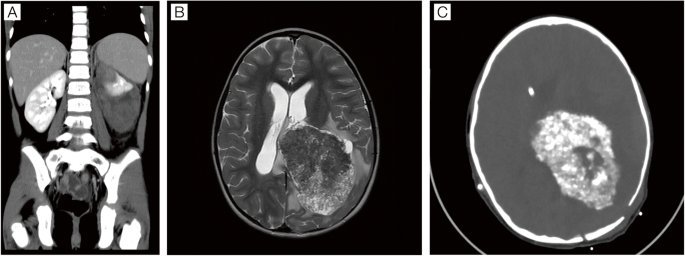

Epithelioid Angiomyolipoma In A Patient With Li Fraumeni Syndrome Rare Pathologic Diagnosis Aace Clinical Case Reports

Synchronous Choroid Plexus Papilloma And Wilms Tumor In A Girl Disclosing A Li Fraumeni Syndrome Hereditary Cancer In Clinical Practice Full Text